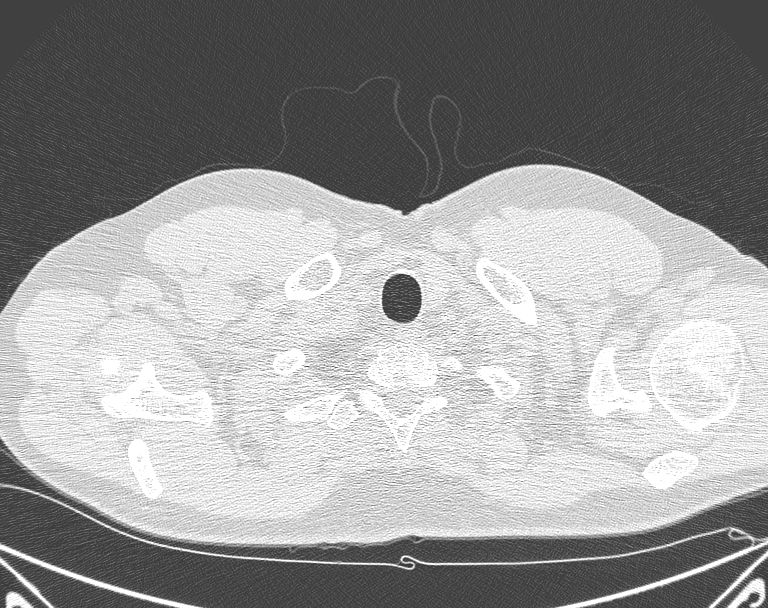

白色文字(排除指定关键词) Imaging Anatomy: interactive PACS-like atlas of radiological anatomy

解剖学模块